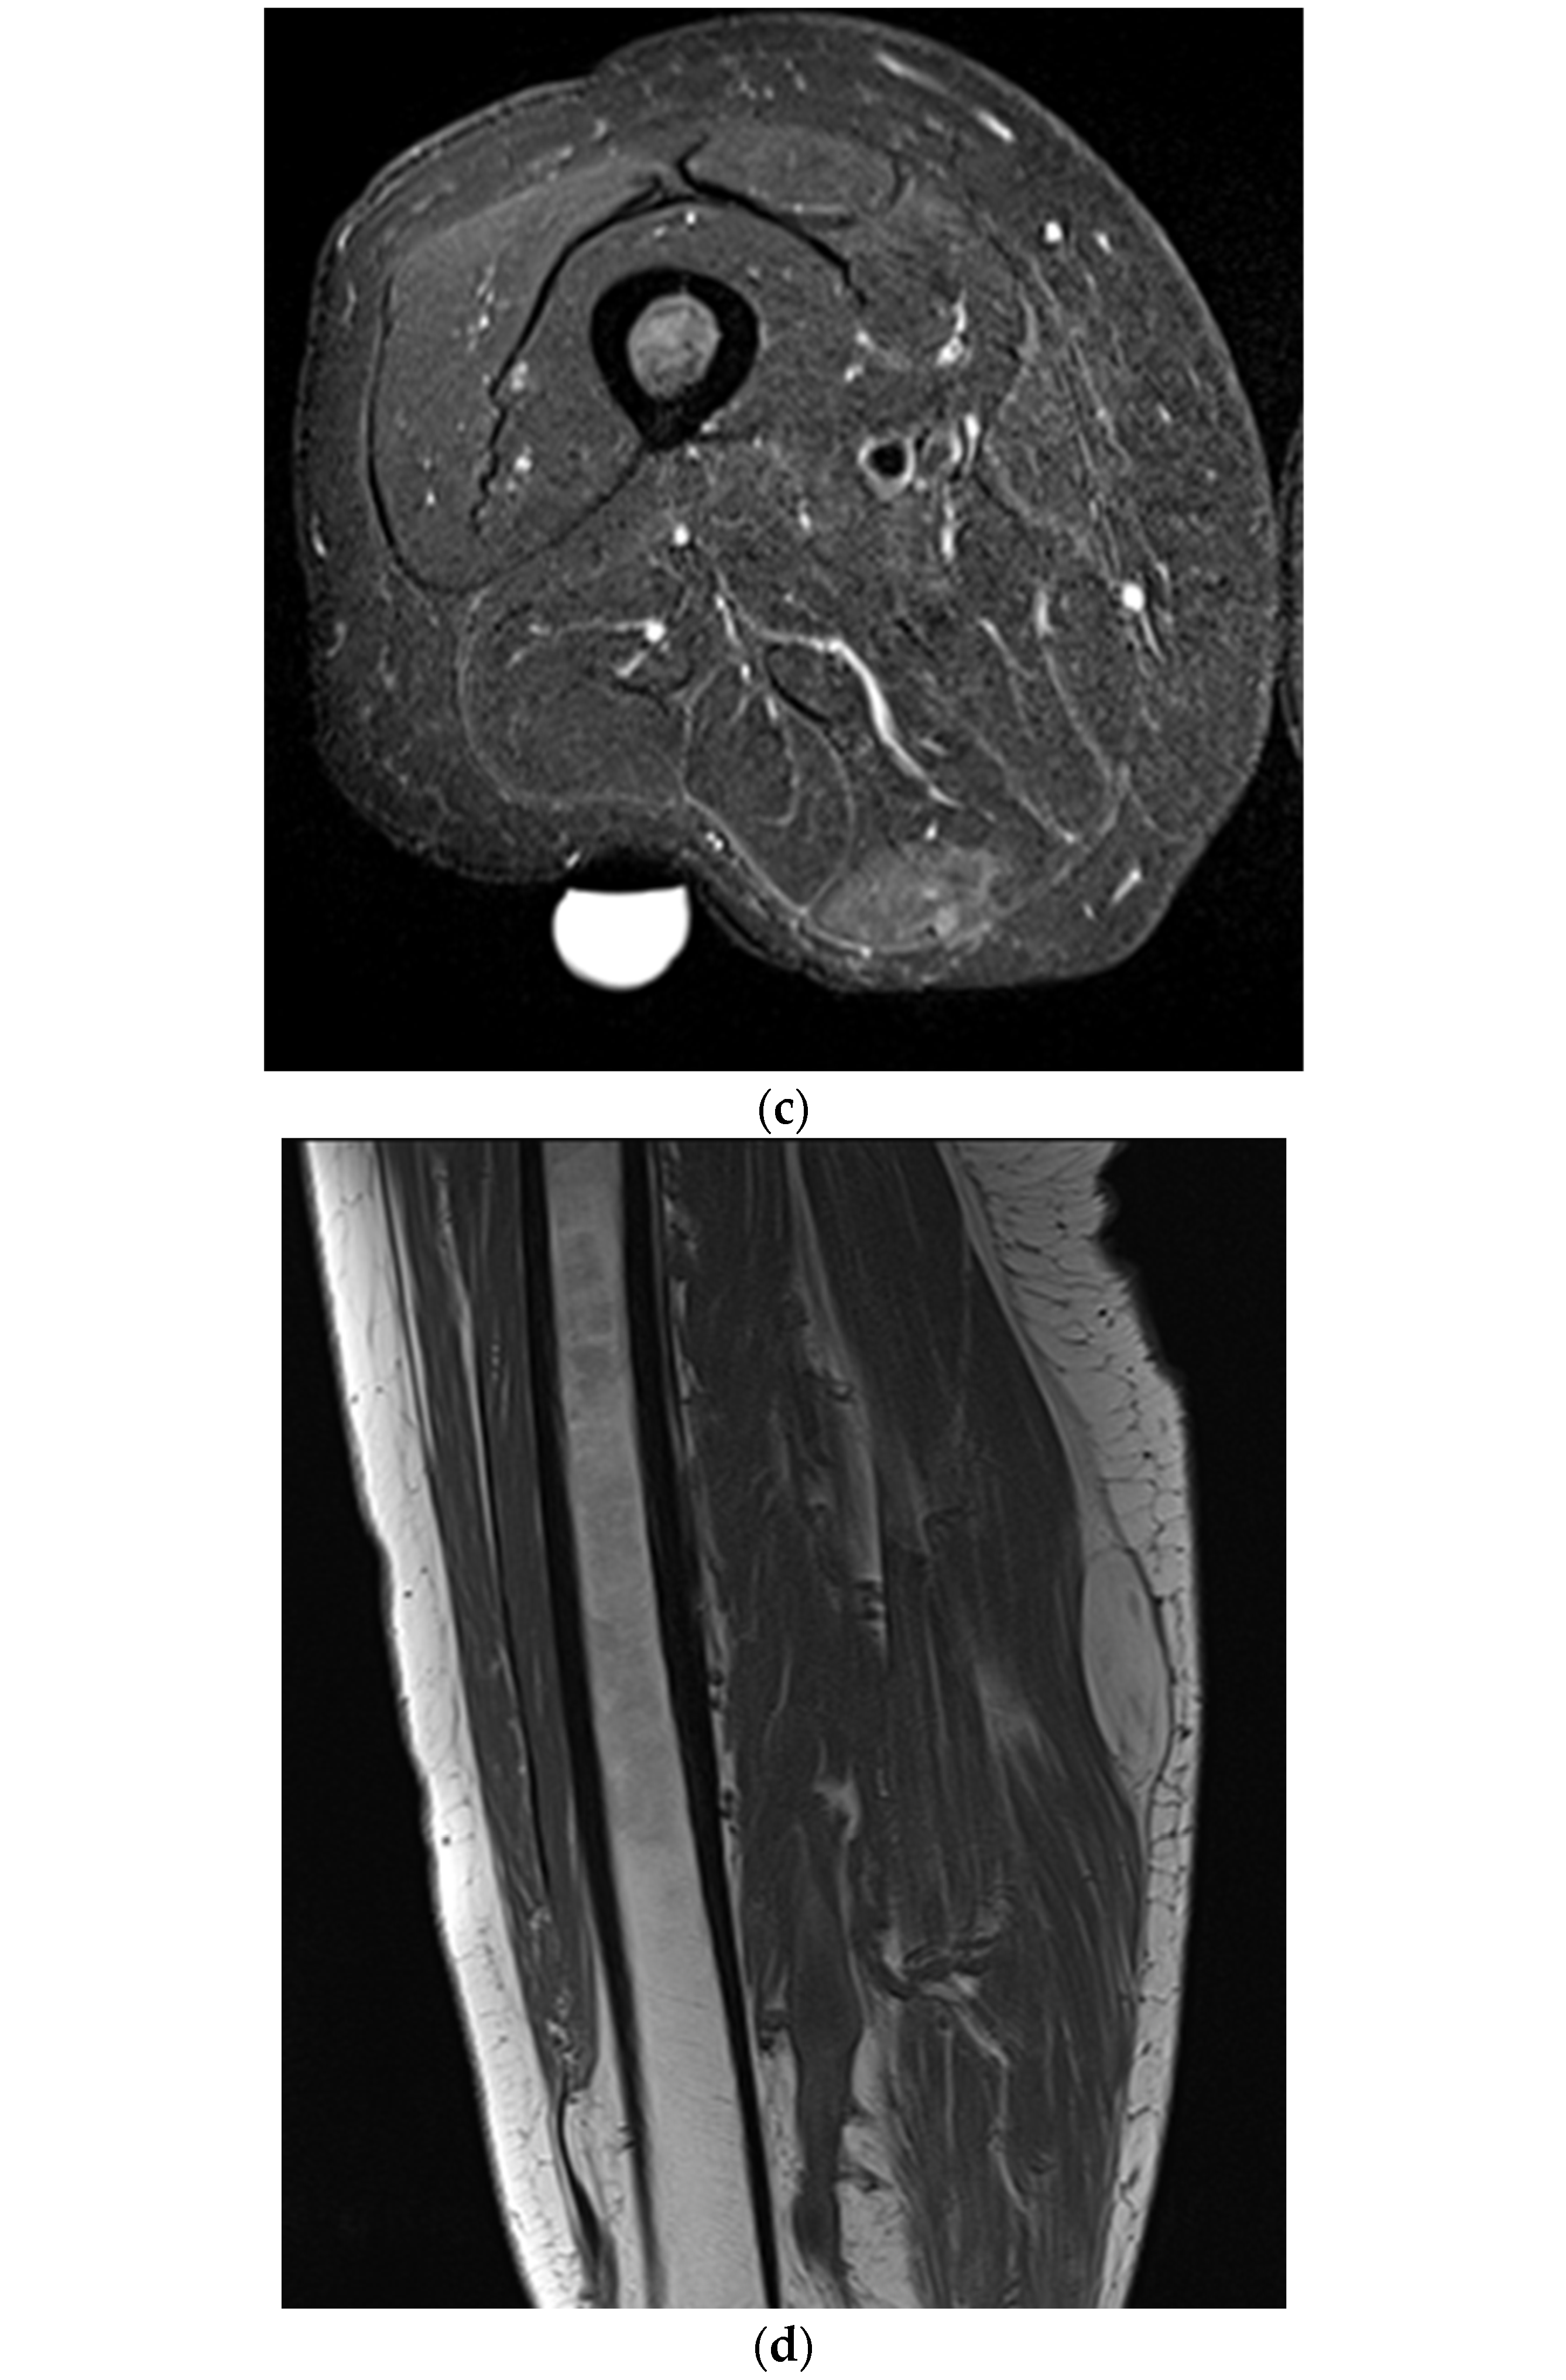

Magnetic Resonance Imaging or Ultrasound in Localized Intermediate- or High-Risk Soft Tissue Tumors of the Extremities (MUSTT): Final Results of a Prospective Comparative Trial

1. Introduction

2.3. Ultrasound

2.4. Magnetic Resonance Imaging